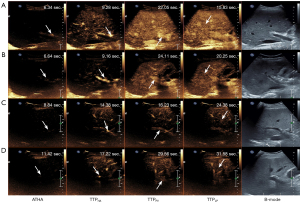

In each uncompressed AVI file, the interval between each frame was 1/12 of a second. Twelve gray-scale images per second were processed using ImageJ software. Contrast images were examined frame by frame, and the time of the first echogenic microbubble observed in the HA was designated as the initial time. Subsequently, a circular ROI with a diameter of 5 mm was placed on the first branch of the HA or PV. Following this, another ROI with a diameter of 10 mm was positioned on the LP, avoiding vessels, and at the same depth as the other ROIs (Figure 2B). After measuring the intensity values of the ROIs, a TIC with a duration of 30 s was generated using Excel (Microsoft, Redmond, WA, USA), commencing from the arrival of the contrast agent at the HA; the arrival time (AT) was also recorded (Figure 2C). Time-to-peak (TTP) and PI were assessed based on the TIC. All TIC parameters were measured two times for each donor to investigate the intra-observer variability. Further, the TIC parameters of all donors were successively evaluated by two radiologists to analyze inter-observer variability.

In relation to the CEUS parameters, the peak intensity of the hepatic artery (PIHA) [163.24 (128.79–186.05) vs. 199.44 (176.95–213.88), P<0.001], the peak intensity of the portal vein (PIPV) [137.59 (119.96–177.79) vs. 185.12 (157.87–208.35), P<0.001], and the peak intensity of the liver parenchyma (PILP) [110.63 (75.88–139.93) vs. 143.72 (120.27–157.51), P=0.001] were significantly shorter in the steatosis group than the non-steatosis group (Figure 3). However, there were no significant differences in the other TIC parameters between the steatosis and non-steatosis groups. As reported in our previous studies (20,21), the intraclass correlation coefficient analysis showed good intra- and inter-observer agreement for the CEUS and TIC parameters.